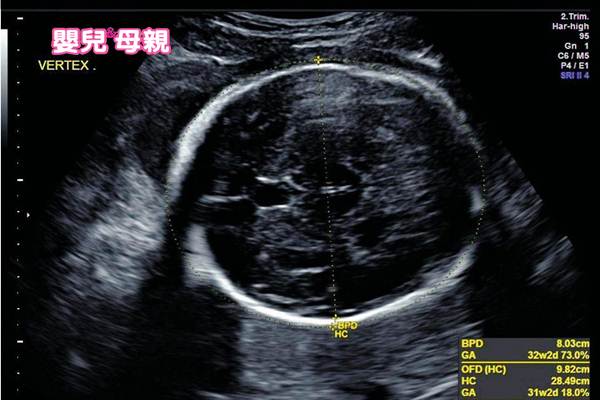

這個時期會開始預估胎兒的體重,如何推估胎兒重量?魏沛秝醫師說明,量胎兒頭骨的橫徑、腹圍、腿骨,再輸入電腦統計,誤差值約為10%至20%;胎兒29至32週重量預估值約為1000g至1500g。

圖說:29至32週,檢查胎位是否往下。